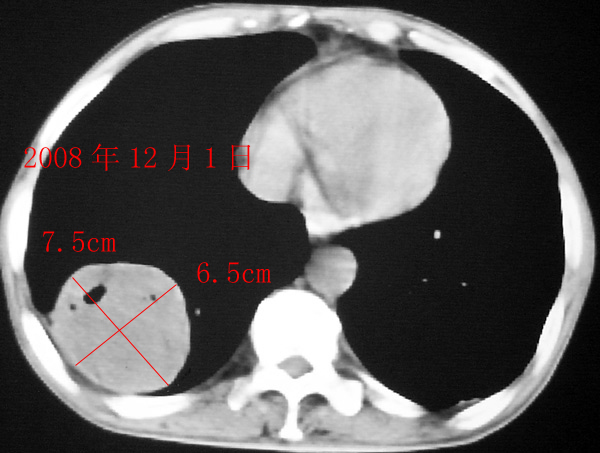

标题: CT15350 今日复查CT

右肺囊实性占位 患者拒绝穿刺活检  近期始终间断性发高烧 使用消炎控制, 左鼻翼部有多发皮肤溃疡

我认为本例肿块内为坏死组织与实性组织混在一起,并夹杂有极低密度气体影,加上肺肿边缘部分呈不规则浅分叶,应该诊断为周围型肺癌。

患者三个月前的ct增强片也显示肿块壁不规则并有明确的壁结节,也支持周围型肺癌的诊断。

如果患者仅是单纯的慢性肺脓疡,在经历了三个多月的治疗后,其内的坏死液化组织与气体应该形形一些短的气-液平面,而本例肿块内没有一个典型的气-液平面。

右下肺占位性病变,其边缘较光整无明显分叶,似有包膜,邻近胸膜无凹陷征及牵拉征象,包块内见数个大小不等气液面及不规则透亮影,纵隔未见明显淋巴结肿大。结合上次ct检查,考虑:炎性包块或真菌感染包块可能性大,周围型肺癌可能性小。

2008年8月19日ct所见为实性肿物,轻度强化,而患者仅有“胸闷、食欲不振”的症状,没有发热病史,因此考虑良性肺肿瘤可能性大。

本次ct检查,在肿块内出现了气体,而且“近期始终间断性发高烧”,考虑肿瘤合并感染可能性。

电话随访:到上级医院手术结果:肺癌

感谢楼主反馈结果。囊实性肿块,壁厚薄不均,壁结节有明显强化,均支持肺癌诊断。